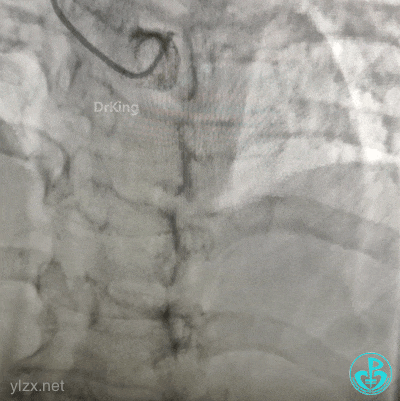

果断更换指引导管。

指引导管刚刚送到升主动脉,患者便发生抽搐、呼之不应,立即胸外按压几次后,患者清醒了,快速置入IABP。造影发现整个前壁不怎么搏动了。

血压低,去甲肾上腺素8mg,25ml/h微量泵入,血压高时可维持在140/80mmHg左右,一直到手术结束。

2.0×15mm球囊预扩张后。